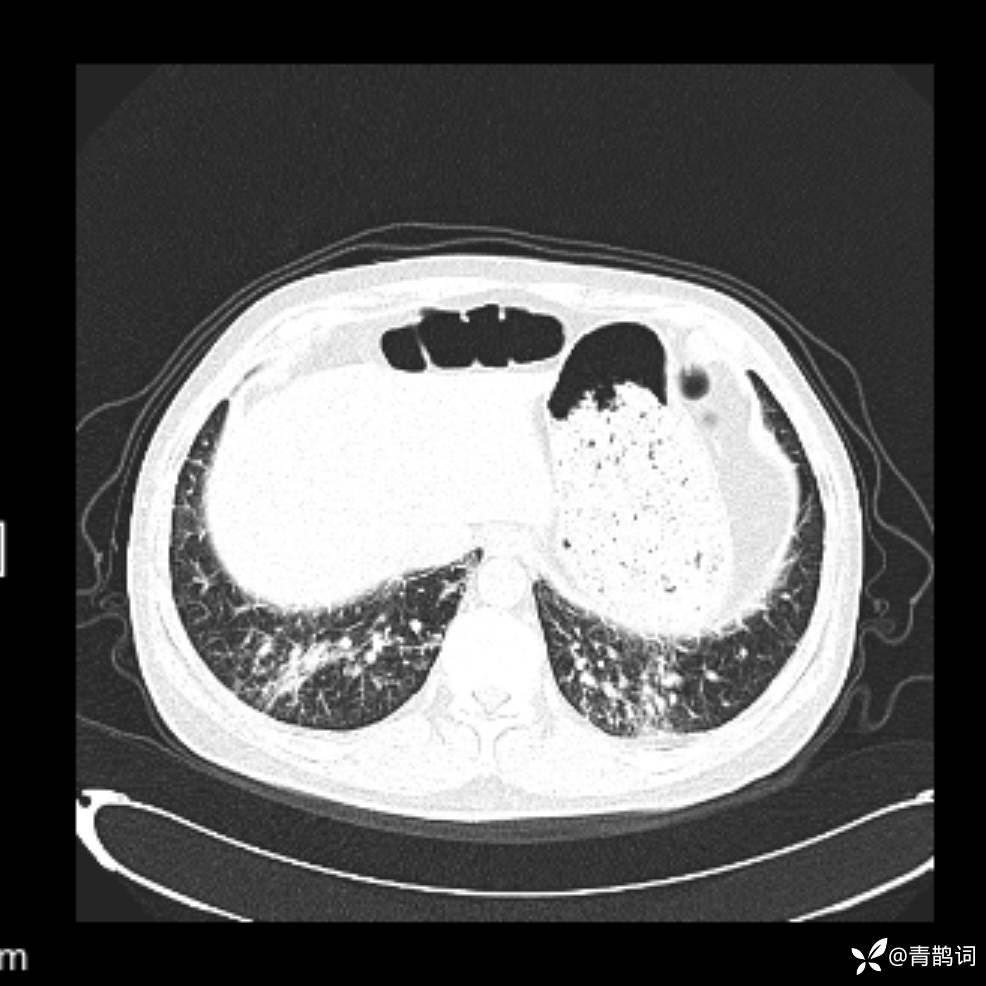

患者年龄:30岁。

患者性别:男。

简要病史:左颜面部肿胀2年,反复咳嗽咳痰,逐渐加重。

结合病史及影像学表现,期待评论区各位老师各抒己见~

木村病 (14)